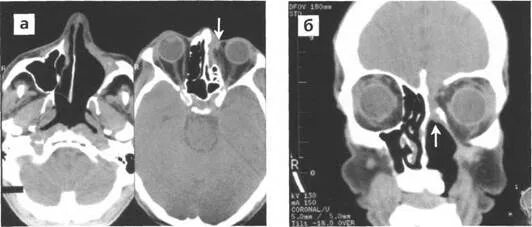

Болит кт